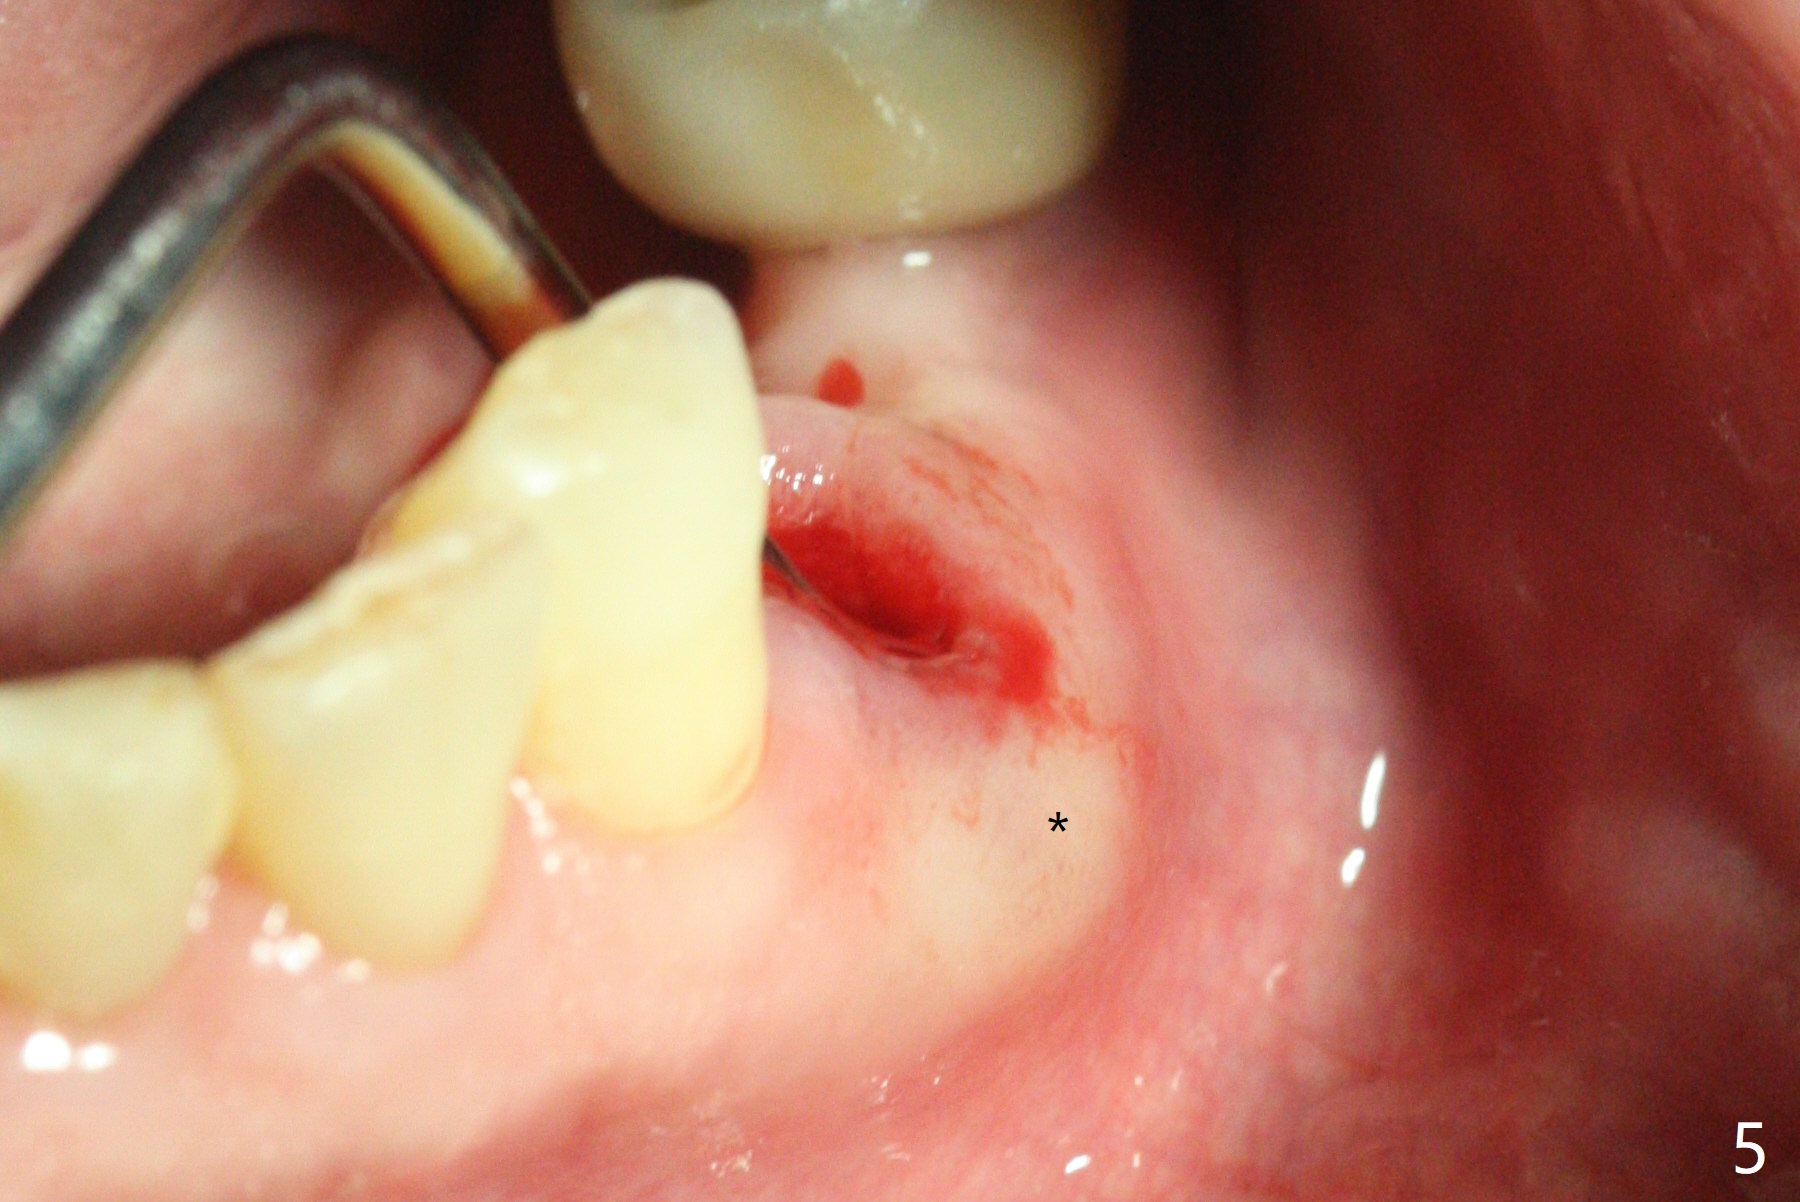

A 73-year-old man with history of stroke presented to office with #20 chewing pain 2 years ago (Fig.1). When he returns today, the tooth #20 has lost, while #21 has mobility (Fig.2), torus mandibularis (Fig.3 *) and severe bone loss, as related to Class V defect (Fig.4). As expected, the buccal plate is lost, the buccal gingiva blanching and bulging due to a curette underneath (Fig.5 *). After placement of allograft in the socket (Fig.6,8 *), a 8x8 mm BioXclude and 4-0 PGA suture are used to close the socket (Fig.7). Periodontal dressing stays in place 10 days postop (Fig.9). The patient is pleased with hemostasis. He is going to return his home state.